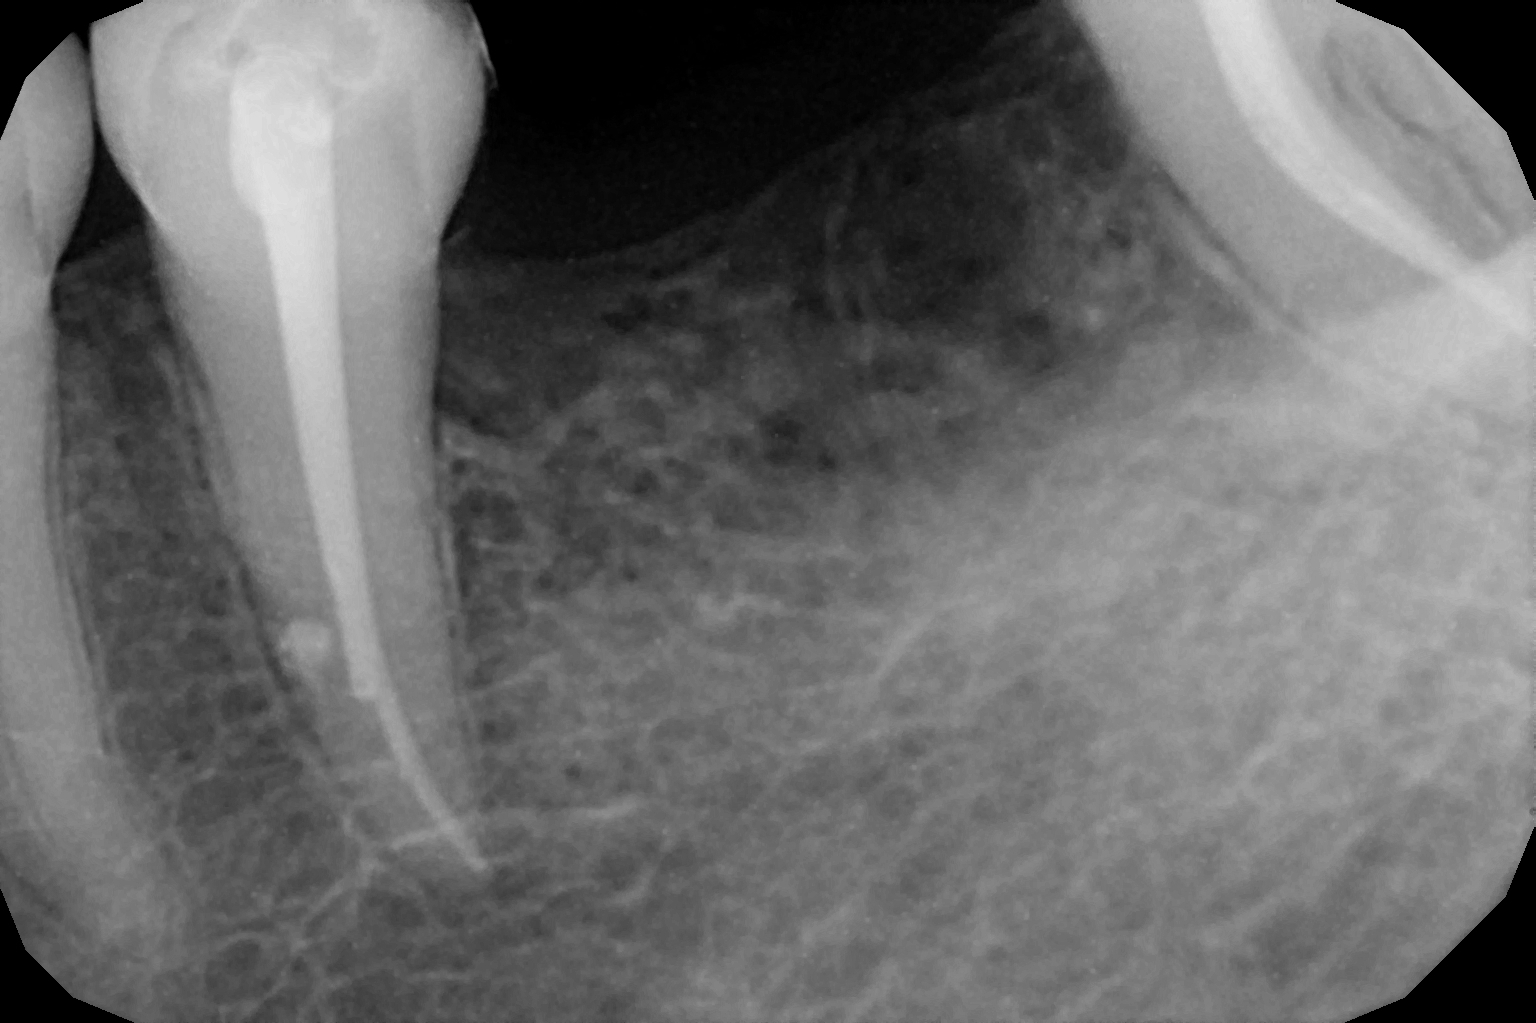

When the tooth is is sensitive to particularly hot and cold. When you cannot chew from that side or there is associated action of pain and swelling with same tooth, root canal treatment can save the tooth. For root canal treatment our clinic is equipped with state-of-the-art facility. We are following the protocol that is universally accepted and considered as a gold standard We are using rubber Dam for maximum possible cases. The root canal treatment is done under local anaesthesia that's why mostly it is painless . The rubber Dam isolation helps in proper irrigation and it provides much needed ease to the operating dental surgeon and the patient . The sealer and filling material are one of the Prime requisite of quality root canal treatment, it needs use of multiple X rays to really judge whether the results are acceptable or not. In older days root canal was just about cleaning the decade portion, removing the Pulp and filling it with biocompatible material but nowadays the root canal treatment it is very much advanced the precision is increased manifold. The materials and armamentarium that is required for efficient root canal have advanced in exclusion initial ways the the Abstract of all these things is the patients are getting great results after root canal treatment. Only the root canal is not sufficient to make a tooth functional again ,it needs use of Core buildup material and complete coverage Crowns according to the tooth position. During Covid19 time we have studied and implemented use of of high strength composites in our practice and the results of it are amazing many times it has saved tooth from being restored with crown. In some cases where the tooth is grossly carious we need a complete coverage crown. The materials and the Crown materials are are available in various price ranges. We prefer only the best of materials for our patients. We believe that to perform best treatment we need best of the armamentarium and best of the material for our patients who value and deserve the best of the treatment.